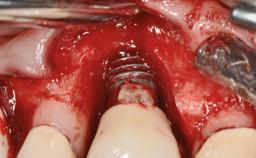

Peripheral Giant-cell Granuloma Associated with Peri-implant Tissues

Defining Characteristics More than three missing teeth to be replaced with an implant-borne prosthesis or prostheses

Placement Protocol Early or late implant placement